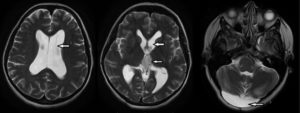

Одним из признаков рассеянного склероза на магнитно-резонансных снимках являются мелкие очаги в головном и спинном мозге, которые выглядят как светлые участки.

На томограммах врач может заметить следующие изменения:

- «Пальцы Доусона» — признак демиелинизации белого вещества головного мозга. Эти образования вытянуты и располагаются вдоль мелких вен, перпендикулярно боковым желудочкам.

- Увеличение сигнала от очагов после введения контрастного вещества.

- Множество поражений в перивентрикулярной зоне.

Если пациент пройдет МРТ через три месяца после начала клинических проявлений, врач сможет обнаружить:

- Множественные очаги, накапливающие контрастное вещество.

- Участки просветления, прилегающие к коре головного мозга и затрагивающие дугообразные волокна.